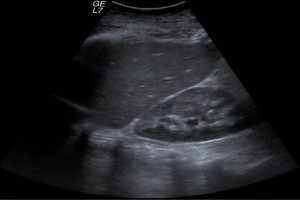

El programa fue diseñado para llevar de la mano al participante y ofrecerle herramientas que le permitan hacer una evaluación radiológica atinada, lo cual lo llevará a un diagnóstico que por ende arrojará el tratamiento idóneo. El énfasis se ha dado en la metodología diagnóstica, que es por inducción, así como el manejo del paciente, para crear una conciencia responsable y humana entre los que se dedican o quieren iniciarse en la práctica de la ultrasonografía. Dado a que existe una aplastante demanda de estudios de ultrasonido ante el insuficiente número de médicos radiólogos certificados, además de que el servicio de rayos x en México ha sufrido de ineficiencia en la aplicación del estudio y elaboración diagnóstica de la patología, la labor de este curso es formar de manera profesional a los médicos para que cubran y aminore en gran medida este problema que habita en el sector de salud.